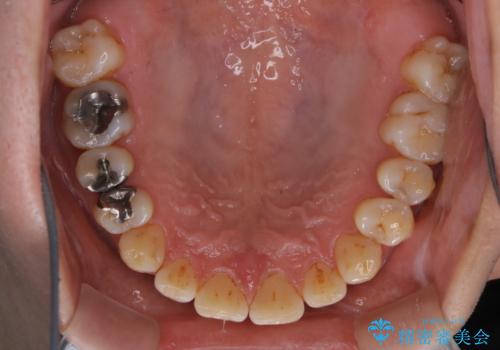

タバコとコーヒーによる頑固な着色落とし

- 毎日の喫煙とコーヒーを飲むことにより、ひどく着色がついてしまったとのことです。PMTC60分コースを行いました。